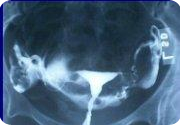

Gebelik Sonlandırılması Amacıyla Yapılan Kürtaj İşleminin Tekniği Nedir?

Kısaca bilgi vermek gerekirse vajina ve rahim ağzı, işlem esnasında mikrop kapmasını engellemek amacıyla dezenfektan sıvılarla temizlenir ve rahim ağzını sabitlemek için plastik bir alet vajinadan yerleştirilir ve genel anestezi için anestezi uzmanı tarafından gerekli ilaçlar verilir. (Çok nadiren lokal anestezi de uygulanabilir.)

Daha sonra çok ince plastik kanüller (borucuk)rahim ağzından rahim içine yerleştirilir. Bazen rahim ağzının genişletilmesi amacıyla daha geniş çaplı plastik kanüller kullanılması gerekebilir. Bu durumda da rahim ağzını genişletmek için buji adı verilen aletler kullanılır.

Kanül yerleştirildikten sonra kanüle bir enjektör iliştirilir. Enjektörde oluşan vakum yardımıyla rahimin içi vakumla boşaltılır.